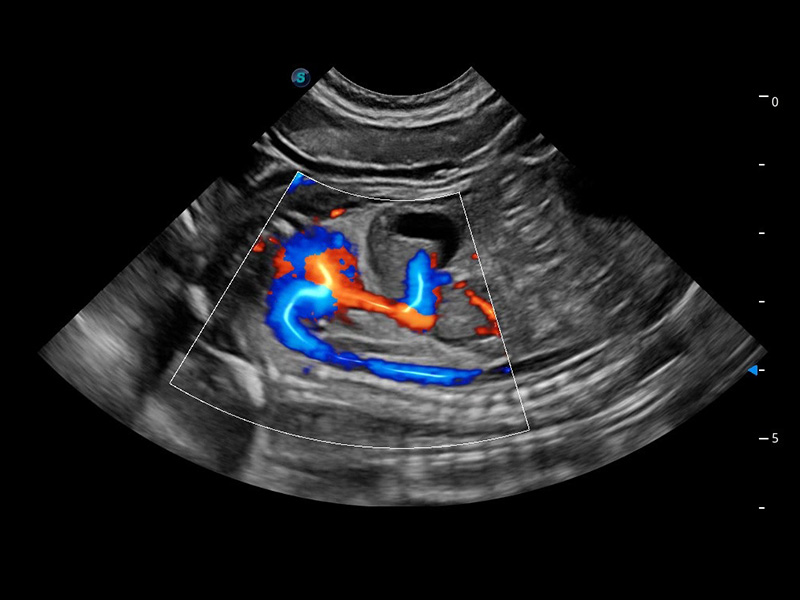

ProPet 60 作为一款高端台式动物超声设备,为动物医生的日常诊断提供了一系列贴合动物临床需求、解决临床实际问题的高级成像功能。凭借全系列高清探头,满足医生对腹部、心脏、生殖、浅表、肌骨等成像的所有需求,切实帮助您提升检查效率,提高诊断信心。

动物是人类最亲密的朋友和最值得信赖的伙伴。乐玩lewin国际也一直致力于探索动物专用的超声影像解决方案。 全新推出的ProPet系列,是乐玩lewin国际在动物超声影像智能化、专业化、精准化的一次跨越式革新。动物不能用言语来表述自己的不适,通过超声影像,ProPet系列搭建了动物医生与不同物种沟通的“桥梁”,为动物医生注入了“治愈之力”。